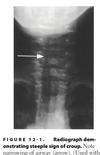

Croup: most common pathogen and key sxs/signs

most common pathogen: Parainfluenza virus key sxs/signs: Barking cough, steeple sign

Key diagnostic sign for croup

Steeple sign—narrowing of tracheal air column just below the vocal cords

Croup: X-ray buzzword?

“steeple sign”

Croup: CXR